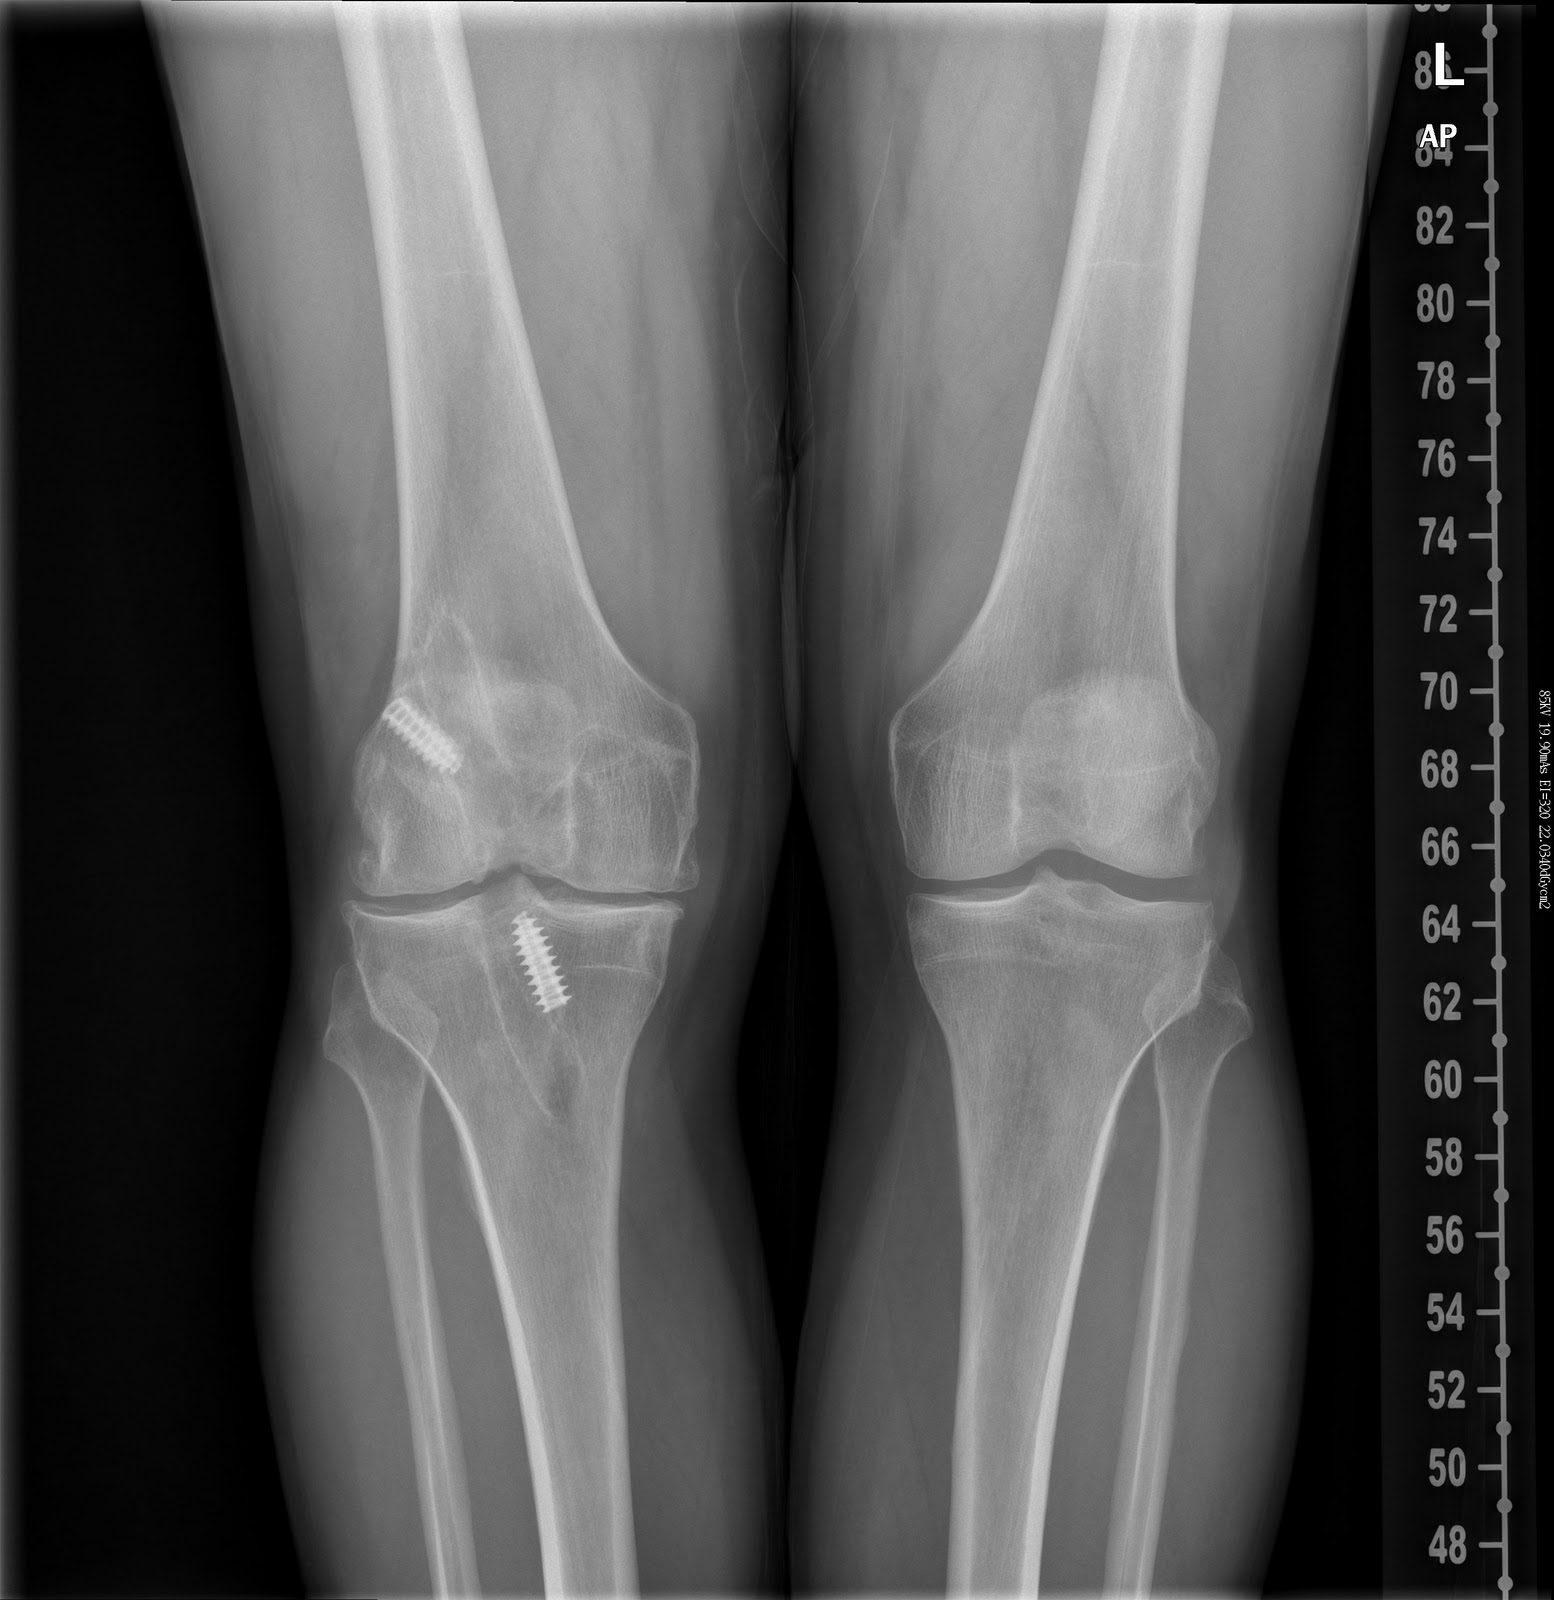

Its now midday here on Saturday 18th December and I am lying on a hospital bed once again....my knee is a disaster. I had a 5 hour surgery!!! It was all a bit tricky in the end. There were 3 specialists on the case. I woke up at 11.30pm in the recovery room and had a fitful and morphine infused nights sleep. I stopped taking the morphine about 3 hours ago (its now 12 noon), as it was doing my head in so to speak!. Now the pain is pretty bad, but at least I am awake and compus mentis. The doctor arrived to check me out a few minutes ago and he told me of the saga.. they have taken my ACL completely out as both the original and the revision were non-functional. then they drilled out the retaining screws and replaced the holes in the base of the femur and top of the tibia with a graft from my hip - A 2cm by 5cm core was hand-drilled direct from my hip, my perfectly functional pelvic bone to facilitate this!! Bits of this section have now plugged the old screw and ACL holes which will, in time fuse with the bone around it filling all the holes back in. They had also taken some slivers of the section and screwed this into the top of my tibia with the aid of a titanium plate. They did this as they felt that by re-aligning my bones, I should walk properly again without an ACL. Also they suggest that this will reduce future problems like those probably caused by the first quack who sliced me apart in Glasgow for the first ACL some 15 years ago and succeeded in crippling me for life.

This current triad of orthopaedic wizardry reckon that I might be able to function reasonably well now without an ACL, but if not, by filling in all the holes, they could take some of my right hamstring and screw it back into the now re-filled holes to act as an ACL. They would normally use my left hamstring, but that was taken in the revision ACL op some 4 years ago. So my right would have to suffice!

The doc says the reason why I am in such bad pain is because they basically did 4 operations in one go. Removal of a lot of torn cartilage (the stuff that cover bones at joints to ensure smooth contact surfaces), removal of 2 torn areas of my meniscus (the rubbery shock absorbing layer between the tibia and femur), the removal of the old ACL and screws - including the refilling with hip bone cores as mentioned yesterday) and finally the re-alignment of the joint using a titanium plate to reduce the same type of problems reoccurring...They have kindly issued me with a DVD of the whole thing! Makes for interesting, if gory viewing. In fact it made me wince with pain as I watched it through.